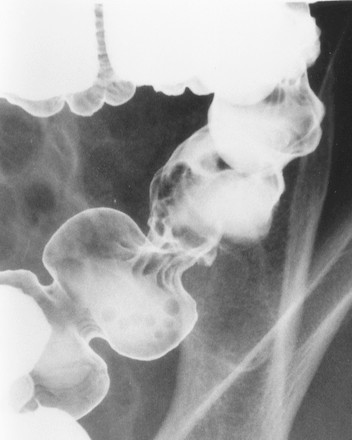

Viêm đại tràng do lao có hình ảnh giống bệnh Crohn, bệnh hiếm ở người da trắng nhưng hay gặp ở người châu Á và bệnh nhân AIDS. Mặc dù phần lớn là thứ phát sau lao phổi, nhưng đa số bệnh nhân không có bằng chứng lao phổi trước đó hoặc lao phổi hoạt động. Với bệnh nhân châu Á, phần lớn bệnh nhân lao ống tiêu hóa là do nuốt trực khuẩn lao bò. Chẩn đoán trực khuẩn kháng axit hoặc u hạt hoại tử bã đậu có độ nhạy thấp (khoảng 32% và 50%, tương ứng) [9]. Với sự hiểu biết tốt hơn về các đặc điểm của viêm lao đại tràng, chẩn đoán sớm bằng chụp cản quang kép là có thể [10]. Các đặc điểm sớm của lao đại tràng là co thắt, tăng tiết, tăng nhu động, tăng sản lympho, các nếp dầy, và các vết loét nông (Hình 18). Các dấu hiệu của viêm lao đại tràng tiến triển khi chụp cản quang kép bao gồm các vết loét ngang (Hình 19), các nốt, các nếp dầy, polyp viêm hoặc sau viêm, hẹp và biến dạng vùng hồi-manh tràng (Hình 20).

Hình 20. Bệnh nhân nữ 41 tuổi. Chụp cản quang kép cho thấy hẹp và biến dạng vùng hồi-manh tràng và đại tràng lên mà không thấy tổn thương niêm mạc hoạt động.